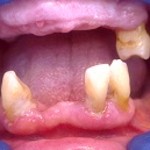

Este é um caso mais simples de se fazer e com um valor (custo-benefício) bastante cómodo.São somente 4 implantes na arcada inferior suportando uma barra sobre a qual será transferido em parte o esforço mastigatório. É confeccionada em RESINA como uma prótese total convencional.